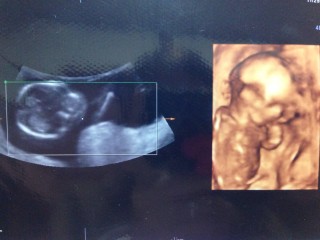

手足がクッキリ映っててお気に入りの写真です。 性別はまだ分からないけど可愛い姿にママパパ共にほっこり! 日に日に成長する我が子に感動しっぱなしです。

順調に大きくなっていて約10cm! 指をしゃぶったり伸びをしたりクルクル動き回っていて安心しました。

蹴ってるのが見れました(*⌒▽⌒*)